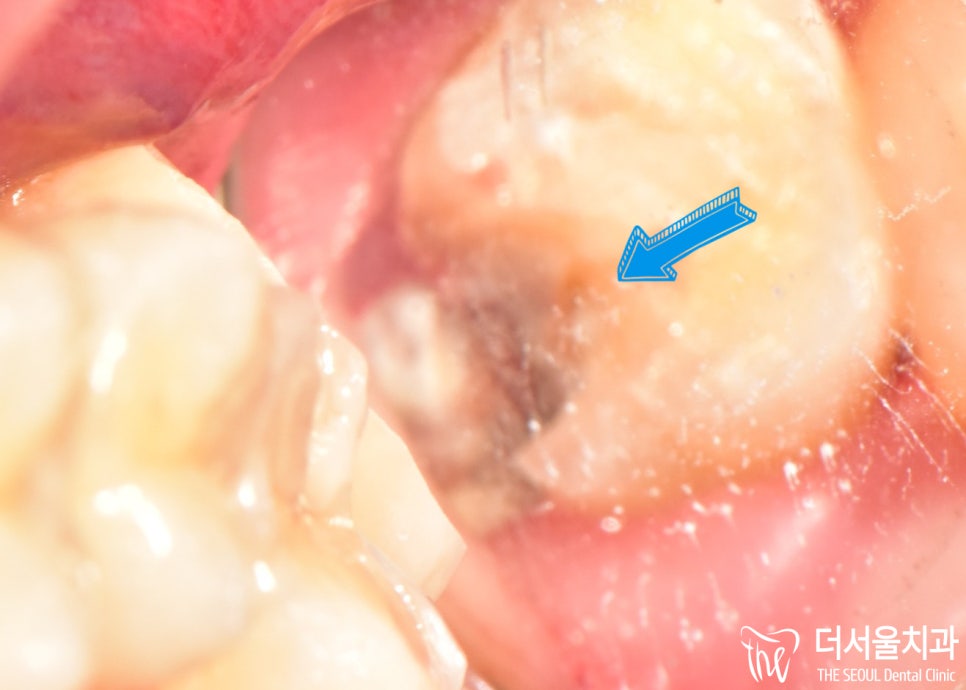

문정동치과 의료진이 해당 부위를

좀 더 확장을 시켜 살펴보니

옆에 시커멓게 변한 곳을 볼 수 있죠?

아무래도 저런 식으로 옆으로 파고 들면,

신경이랑 가깝기 때문에

치아 수명은 더욱 짧아질 수밖에 없습니다.

치관에서 시작된 것이라면,

그나마 다행이었을텐데 말이죠.

어금니 머리 부분은 멀쩡한데,

옆이 시커멓게 썩은 것을 보면

정말 심하다는 것을 느낄 수 있죠?